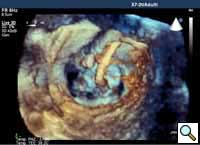

Percutaneous mitral repair using the MitraClip® system (Evalve, Inc., Menlo Park, CA USA) is a method derived from the double orifice open heart surgical technique. According to this technique, mitral regurgitation (MR) is treated by suturing the free edges of the opposing leaflets at the site of regurgitation. The surgical procedure was introduced in clinical practice more than 15 years ago [1], and has proven early efficacy and durability in various anatomic and functional lesions. The MitraClip system reproduces the surgical procedure using a clip to join the opposing leaflets at the location of the MR origin [2]. The system includes the MitraClip device (Figure 1) and a sophisticated delivery system (Figure 2) which is used under echo guidance.

In absence of controlled clinical trial data which are forthcoming from the EVEREST II randomized study, the indications for the MitraClip therapy are currently based on registry experience and will evolve as the technique improves, experience is growing and the data to demonstrate efficacy and safety becomes available. At this time, the best indication for the MitraClip therapy is for symptomatic patients with clinically significant functional or degenerative MR who are at high or increased risk for open heart surgery. From a pure technical standpoint, the procedure so far has only been demonstrated in a subgroup of patients with specific anatomical characteristics which are summarized below and shown in Figure 3. Anatomic suitability is assessed by transesophageal echocardiography, and mitral regurgitation should originate from the central portion of the valve involving the A2-P2 segments, since the device is not ideal to work in the commissures at this time; the mechanism of MR can be either a prolapse/flail or MR due to restricted leaflet motion unrelated to rheumatic disease; the separation between the two leaflets at the site of regurgitation should be limited; severe annular dilatation and/or severe calcification should be absent or is relevant. In case of flail, the flail segment width should be less than 15 mm, and the flail gap less than 10 mm. Figure 4 is a 3D echo image of a patient with posterior leaflet prolapse selected for MitraClip therapy. In case of functional MR, the leaflets should have a minimal residual tissue available for coaptation with the MitraClip device. Figure 5 shows 2D color Doppler jet extension over the coaptation line at TEE short axis transgastric view, while Figure 6 shows the tenting area and the coaptation depth of a patient undergoing MitraClip implant.